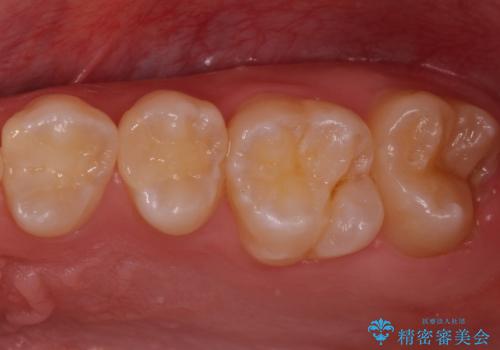

歯と歯の間の虫歯 セラミックインレーでの治療

外から見て虫歯がないように見えても実は歯の中で大きく広がっていた、というケースは多く見受けられます。

症状なく進行していくことも少なくないため、定期的な検査はとても重要になってきます。

今回は残せる歯の厚みが十分確保できたため、インレーでの修復処置となりました。